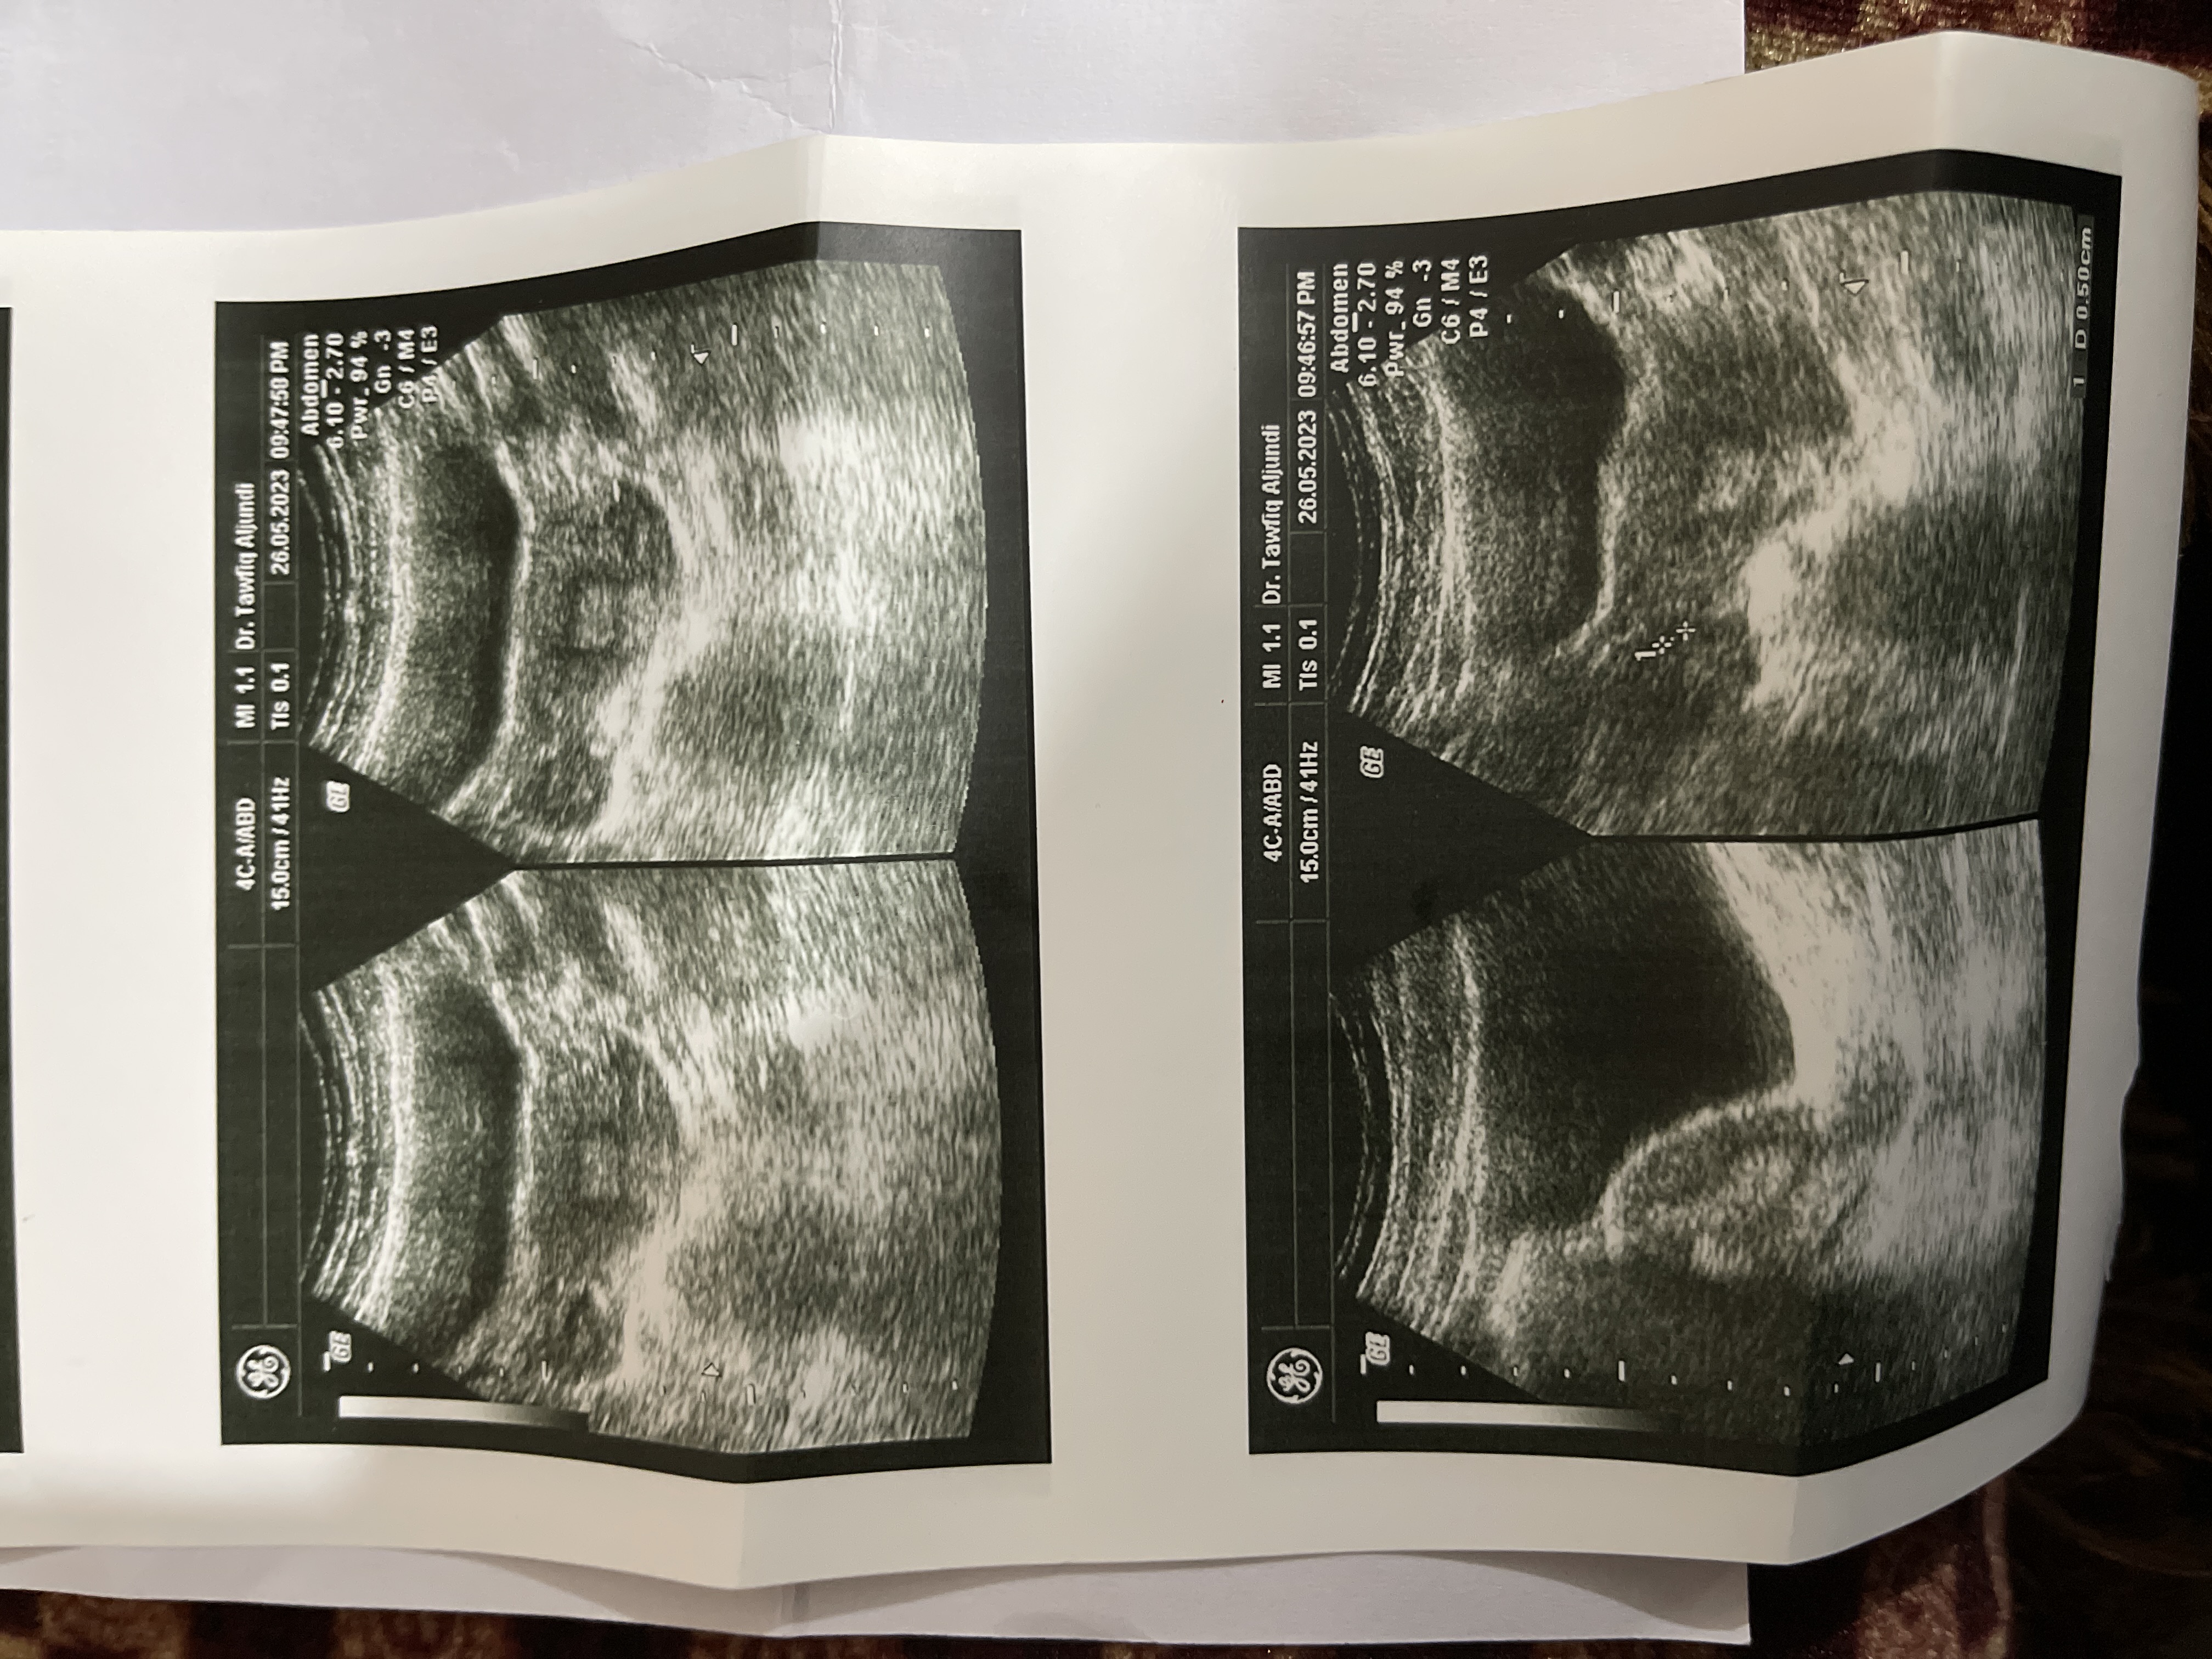

عندي كيس في الرحم وعندي نشاط المبايض